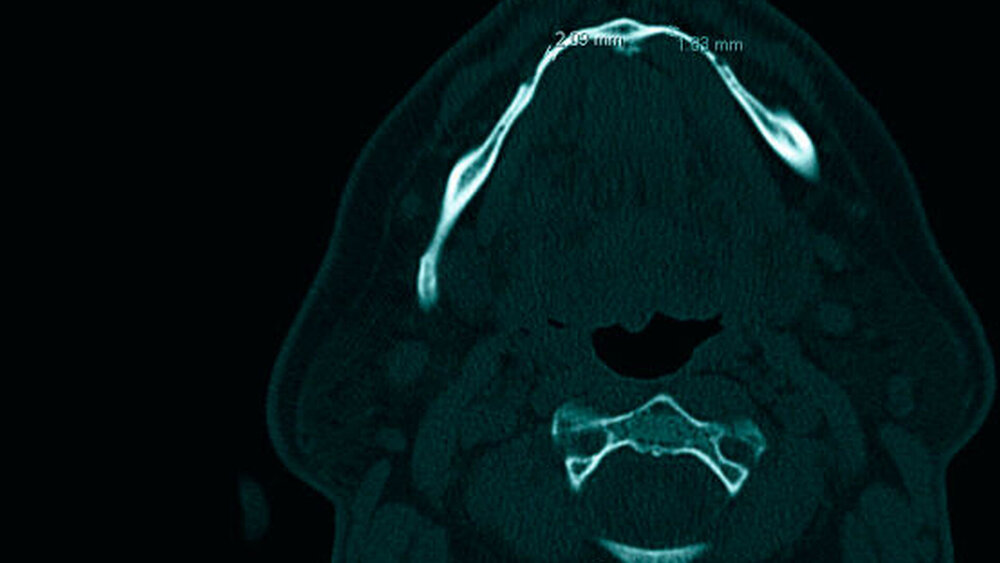

Dort stellte sich der Alveolarfortsatz im Unterkiefer regio 35 bis 45 sanduhrförmig dar (Abbildungen 4 bis 6), stellenweise nur zwei Millimeter stark und mit offensichtlich lediglich kortikalen Strukturen. Im Bereich der Muskelansätze verbreiterte sich die Mandibula entsprechend der anliegenden Belastung, korrespondierend dazu an den Alveolarfächern ebenfalls.